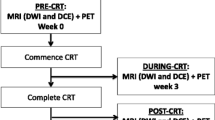

This initial search for patients with at least a pre-therapeutic MRI and primary rectal adenocarcinoma yielded a total of 812 patients (1/1/2007 to 1/27/2013). Given that post-operative re-staging was not performed uniformly or regularly at our institution until 2010 as well as the increasing use of induction chemotherapy or definitive chemotherapy at our institution, most patients did not meet the inclusion criteria above, resulting in a total of 26 homogeneous patients with available post-therapeutic MRI examination. Of these, one patient had to be excluded due to the placement of a rectal stent before post-treatment MRI interfering with imaging, and another patient was excluded due to partial excision of the tumour before MRI. The final cohort therefore consisted of 24 patients (see Fig. 1). Three patients were excluded from analysis of DW imaging, because no DW-MRI sequence was available (n=2) or because of imaging artefacts (n=1). The median interval between the two MRI examinations was 96 (range: 71–131) days, and the median interval between a second MRI and surgery was 20 (range: 3–54) days. All patients underwent standard long-course chemoradiation with 50–50.4 Gy in 25–28 fractions and application of 5- fluorouracil between the first and the second MRI, according to National Comprehensive Cancer Network (NCCN) guidelines [28].

Two readers with experience reading rectal MRI (Reader 1: AMH with 5 years of experience; Reader 2: MJG with 10 years of experience) independently assessed each pre- and post-treatment MRI, blinded to clinical and histopathological information. They each assessed the following metrics, which were chosen either because they were already frequently used for tumour assessment or because they had been reported to provide significant value in response assessment on rectal MRI after therapy (see Fig. 2 a–d for examples):